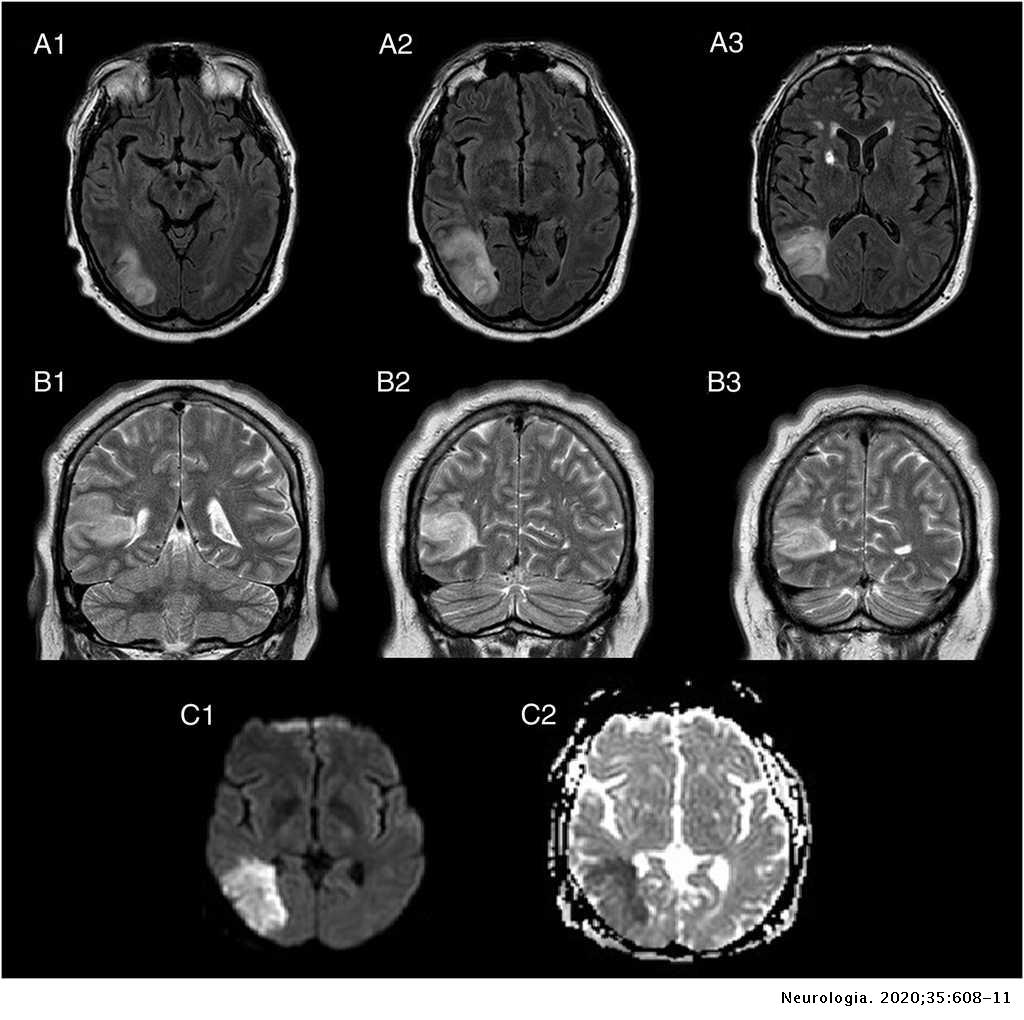

Engineer Team : RESONANCIA MAGNETICA Magnetic Resonance Imaging – Clinical Images Hallazgos por resonancia magnética cerebral de nuestro paciente. M, 21 … Imágenes por resonancia magnética anormales como predictoras de mal … Imágenes por resonancia magnética anormales como predictoras de mal … Lesiones en resonancia magnética (RM) del encéfalo y la médula espinal … Pin en Resonancia Magnética del Encéfalo A) Resonancia magnética cerebral (RMC) mostrando infartos en … Caso 1: Edema cerebral visualizado mediante RM. (A) Secuencia T1 plano … Rascacielos dormir pasta tac y resonancia diferencias retrasar … Pin on Apuntes de Enfermería y T.C.A.E Resonancia magnética cerebral secuencia T2, que muestra lesión … Meningitis aguda en la enfermedad de Behçet | Reumatología Clínica Resonancia magnética coronal normal del cerebro Fotografía de stock – Alamy Imágenes de resonancia magnética, la imagen de la cabeza en diferentes … Resonancia magnética cerebral A) protocolo T1 sagital (Caso 1). Se … Resonancia magnética cerebral. Secuencia T1 corte sagital. Atrofia … Resonancia magnética de cerebro, cortes axiales, secuencias T2. Señal … Resonancia magnética de cráneo. A y B) Cortes axiales FLAIR … Resonancia magnética (RM) de cerebro, corte axial ponderado en T2: la … RM cerebral: Interpretación paso a paso | Kenhub Resonancia magnética de cerebro, cortes axiales, secuencias T2. Señal … De Resonancia Magnética De Cerebro Foto de archivo – Imagen de arteria … Top 107+ Imagenes de resonancia cerebral normal – Destinomexico.mx -Imagen por resonancia magnética del cerebro. a) Cortes sagital y axial … resonanCia magnétiCa Cerebral donde se observa hiperintensidad a nivel … MRI (Imagen de resonancia magnética) – Tomografía computarizada de la … Meningioma – NCI Imágenes por resonancia magnética coloreadas del cerebro sano del … Resonancia magnética cerebral en secuencia FLAIR, que muestra lesiones … Contraste resonancia magnetica cerebral – senturinthegreen Relación de los espacios de Virchow-Robin con la enfermedad de … Gliomatosis cerebral – Instituto Nacional del Cáncer Pin en Neurology. Recomendaciones para la utilización e interpretación de los estudios de … Fotografía De La Proyección De Imagen De Resonancia Magnética Del … atmósfera Dirigir Cumplir anatomia resonancia magnetica Desarrollar … Pin en #MEDICINA,#SALUD Resonancia magnética de la nasofaringe De Resonancia Magnética De Cerebro Foto de archivo – Imagen de polilla … Atrofia cortical global de predominio parietal en la Resonancia … Resonancia magnética cerebral | Download Scientific Diagram Neuroblog: Resonancia magnética cerebral en la trombosis crónica de … De Resonancia Magnética De Cerebro Imagen de archivo – Imagen de … ¿Cuáles son los riesgos de la resonancia magnética? – Integra Salud … Resonancia magnética cerebral al decimocuarto día de ingreso: área … Resonancia magnética. Corte axial mostrando área infartada en el … Resonancia magnética cerebral del paciente AV evidenciando lesiones en … -Ressonância magnética de encéfalo mostrando múltiplas imagens … Resonancia magnética cerebral secuencia FLAIR (Fluid Attenuated … Resonancia magnética cerebral con protocolo de epilepsia, en sección … Resonancia magnética cerebral en corte sagital. Se observa una evidente … Resonancia magnética craneal en la que se evidencian lesiones … Logran visualizar el cerebro a detalle más completo tras una resonancia … Así decide el cerebro la severidad de un castigo De Resonancia Magnética De Cerebro, Imagen de archivo – Imagen de … A) Resonancia magnética cerebral; Secuencia Tof: oclusión de arteria … Un estudio asocia la ansiedad con la aparición rápida del Alzheimer IMÁGENES DE 18 F-PR04.MZ PET FUSIONADA CON RESONANCIA MAGNÉTICA … Imágenes por resonancia magnética anormales como predictoras de mal … Tumores de la región pineal – Instituto Nacional del Cáncer Epilepsia: una historia de voces y fantasmas | Neurología Contribución de las imágenes de resonancia magnética por tensor de … Resonancia magnética secuencia T2 plano coronal de quiste epidermoide … Resonancia Magnética Cerebral del paciente: a. Aumento de… | Download … Resonancia magnética cerebral 2022 Síndrome de hemiconvulsión-hemiplejía-epilepsia. Seguimiento de un caso … Enfoque Radiologico: La resonancia magnética permite detectar lesiones … Resonancia magnética craneal T1 con contraste que muestra angiomatosis … guidewiz – Blog Resonancia magnética cerebral, secuencia SWI. Ribete hipointenso en la … resonAnCiA mAgnétiCA de ColumnA Con gAdolinio. Corte sAgitAl en t1 de … SEMANA 12: FUNDAMENTOS DE RESONANCIA MAGNÉTICA NUCLEAR. INDICACIONES Y … DIAGNÓSTICO DE ESCLEROSIS MÚLTIP Magnetic resonance imaging of the brain – Alchetron, the free social … Resonancia magnética de órbitas | Instituto Radiológico Dr. E Castillo Alteración de la marcha en un paciente post-trasplante hepático Resonancia magnética cerebral de un paciente sano (Ay B) y paciente que … Utilidad de la resonancia magnética craneal para el diagnóstico de la … Resonancia Magnética Del Cerebro El Tumor Cerebral Foto de stock y más … De Resonancia Magnética De Cerebro Imagen de archivo – Imagen de … ABDALLA RADIOLOGIA: NEURINOMA ACUSTICO Atrofia cortical global de predominio parietal en la Resonancia … Resonancia Magnética : Producción de la imagen MRI Brain Scan — Stock Photo © Bunyos30 #18724051 Mri (imagen de resonancia magnética) Monitor con imagen de captura de … Tomografía computarizada vs resonancia magnética: diferencia y … Tumores Cerebrales – Unidad de Neurocirugía RGS Resonancia magnética de la columna, sección sagital. Observe los discos … La resonancia magnética, una técnica imprescindible en el diagnóstico … Perfusión Cerebral por Resonancia Magnética | ¿Qué es? ¿Necesita Contraste? Resonancia Magnética Cerebro A: resonancia magnética, T2 coronal preoperatoria; se observa lesión en … Resonancia magnética cerebral — Foto de stock © Bunyos30 #27340623 La resonancia magnética se perfila como detector de mentiras | Futuro … Resonancia magnética cerebral en T1 con gadolinio, cortes axial (a … MRI brain : show brain tumor at right parietal lobe of cerebrum — Stock … NEUROIMÁGENES EN ENFERMEDAD DE PARKINSON: ROL DE LA RESONANCIA …